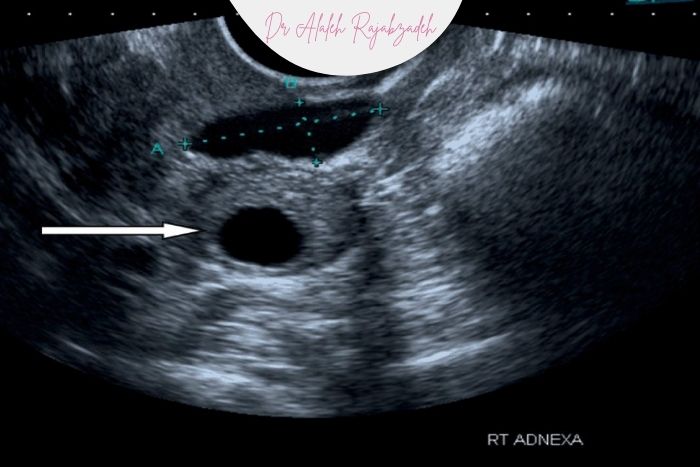

در صورتی که هر یک از ویژگیهای زیر دیده شود کیست دیگر «کاملاً ساده» محسوب نمیشود و پیگیری لازم است:

دیواره ضخیم

سپتوم (جدار داخلی)

توده جامد در داخل کیست

نبضپذیری (vascularity) در داپلر

محتوای غیرشفاف یا اکوهای داخلی

این موارد میتوانند احتمال کیستهای پیچیده یا ضایعات غیرخوشخیم را افزایش دهند و نیاز به پیگیری دارند.